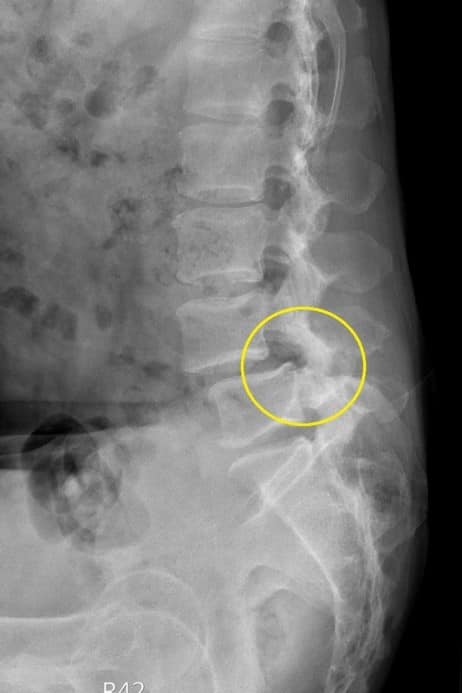

髖關節疼痛要仔細查找腰椎滑脫可能問題!!

除非滑脫第三級且坐輪椅拿拐杖才考慮開大刀